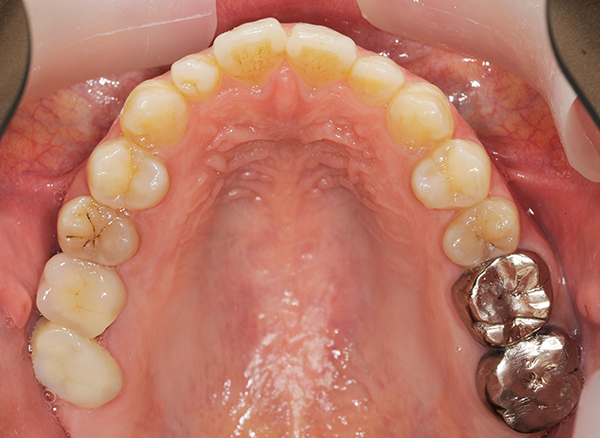

親知らずを大臼歯として生え変わらせたケース

上顎の左右第二大臼歯の予後が悪い為に抜歯を行い、親知らずが大臼歯の場所に生え変わるまで待ちました

抜歯後、親知らずが徐々に生えてきいき健全な歯に生え変わりました。

治療期間 3年

費用 抜歯2本5,000円

| メリット | 抜歯を行うだけなので、治療費や負担が少ない |

|---|---|

| デメリット | 親知らずが生えるまで個人差がありかなりの期間がかかる |